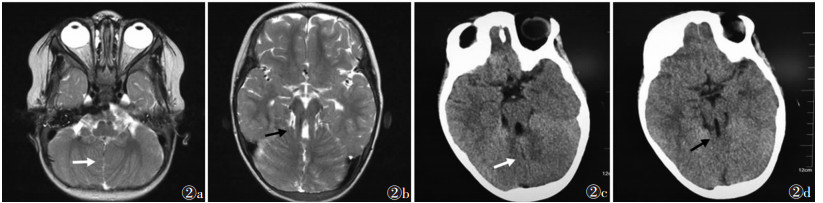

2 结果4例的MRI及CT特征:①小脑半球“中线裂”,小脑蚓部完全或部分缺损致两侧小脑半球紧密靠近而不相连,脑脊液进入其中并与前方第四脑室相连(图 1a,1b,2a),其中2例小脑蚓部完全缺损,2例小脑下蚓部缺损;②“臼齿征”,中脑脚间池凹陷增深,中脑峡部(中脑与桥脑连接部)变细,形成“臼齿”的“牙冠”,小脑上脚增厚、延长,并水平走行(图 1d),与第四脑室顶部形成“臼齿”的“牙根”(图 1c,2b~2d);③“蝙蝠翼状”、“三角形”第四脑室,中脑和桥脑连接部第四脑室呈“蝙蝠翼状”改变(图 1b),第四脑室中部呈“三角形”改变(图 1a)。1例合并枕大池扩大(图 1b)及幕上后纵裂永存镰状窦,1例脑白质髓鞘化发育落后于同龄,1例额颞部蛛网膜下腔增宽。

| 图 2 女,2岁,发育落后,精神发育迟滞,肌张力偏低 图 2a,2b 轴位T2WI示“中线裂”(白箭)及“臼齿征”(黑箭),小脑蚓部全部缺损 图 2c,2d CT轴位平扫示“中线裂”(白箭)及“臼齿征”(黑箭) |

MRI是诊断Joubert综合征首选的影像学检查方法。Joubert综合征的MRI、CT特征性表现有“臼齿征”、“中线裂”及“蝙蝠翼状”、“三角形”第四脑室,三者均由于小脑蚓部发育异常所致。本研究4例MRI扫描均有上述3种表现,其中1例通过CT与MRI图像对照,在显示“中线裂”及小脑蚓部缺损程度方面MRI优于CT(图 2),同时MRI能直接从矢状面观察小脑上脚的形态。“中线裂”是由于小脑蚓部完全或部分缺损造成两侧小脑半球靠近而不相连,脑脊液进入其中并与枕大池及第四脑室相连而成的“裂隙状”影,MRI表现为线状长T1长T2信号,CT表现为线状低密度影。小脑蚓部发育异常可导致第四脑室增大,形态异常,上部“蝙蝠翼状”及中部“三角形”改变。